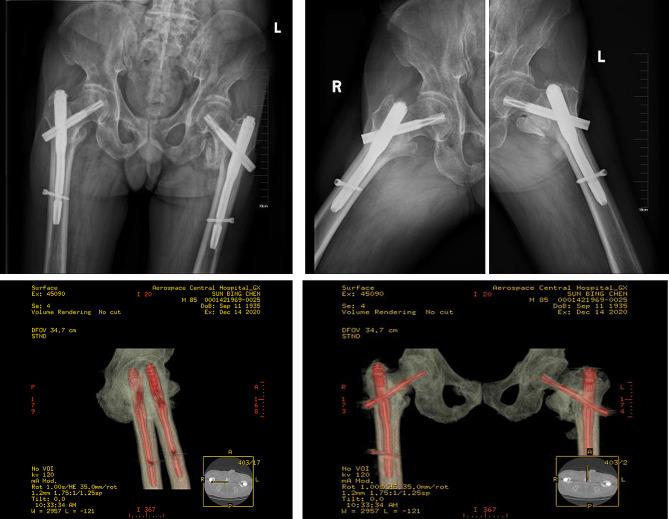

We report on an 84-year-old male who suffered severe trauma from a car accident, resulting in multiple injuries and shock state, with pain and limited mobility in both hip joints. After examination and imaging studies, the patient was diagnosed with multiple injuries and bilateral intertrochanteric fractures. Following emergency resuscitation, he was admitted to the orthopedic ward. A pre-surgical multidisciplinary team (MDT) consultation was convened to optimize surgical conditions. The patient underwent successful one-stage bilateral intramedullary nailing. The patient was assisted to stand with a walker on the third day after surgery. Six months post-surgery, the patient resumed outdoor activities.

我们报告了一例 84 岁男性患者,因车祸遭受严重创伤,导致多发伤和休克状态,双侧髋关节疼痛且活动受限。经检查和影像学研究,患者被诊断为多发伤和双侧转子间骨折。在紧急复苏后,他被收入骨科病房。为了优化手术条件,进行了术前多学科团队(MDT)会诊。患者成功接受了一期双侧髓内钉固定术。术后第 3 天,患者在助行器的辅助下站立。术后 6 个月,患者恢复户外活动。